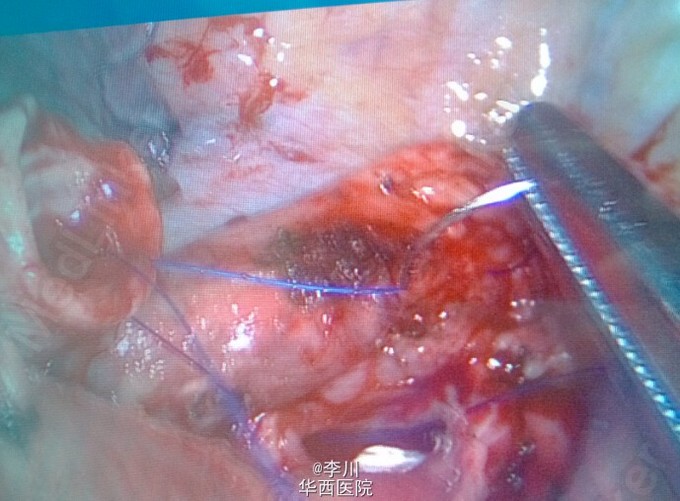

大医院技术更好?---右上肺鳞癌伴肺不张一例

患者为50岁男性,因咳嗽咳痰、痰中带血3+月入院。3+月前患者因上述症状于当地医院就诊,行相关检查后诊断为右肺上叶鳞癌。却被告知不能手术,只能放化疗。患者不甘心,遂于我院就诊,经我院知名专家详细读片评估后,认为有手术指证,首选手术治疗。查体心腹无特殊异常。右上肺呼吸音弱,未闻及干湿罗音,左肺呼吸音无明显异常。